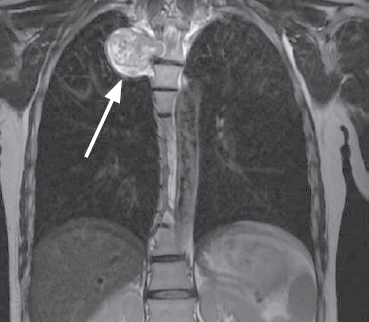

Paravertebral tumors of mediastinal localization — an extensive group of pathological processes, the surgical treatment of which is carried out by doctors of various specialties, such as neurosurgeons and surgical oncologists. Currently, thoracoscopic removal is considered to be the most preferred method of surgical treatment of these mass formations, in view of the least trauma, fewer complications, and a reduction in the time of postoperative recovery of patients. A clinical case of surgical treatment of a patient with a giant paravertebral tumor originating from the 4th thoracic root is presented. The tumor was an incidental finding during routine fluorography. There were no focal neurological symptoms. Taking into account the topographic and anatomical features of the volumetric formation, the patient underwent a combined two-stage surgical intervention, where the first stage was laminectomy and removal of the foraminal component of the tumor from the posterior approach, the second stage was single-port video-assisted thoracoscopic removal of the mediastinally located tumor fragment. The operation was performed under conditions of a collapsed lung on the side of the intervention. In the postoperative period, no neurological deficit was noted; according to the control introscopy, the tumor was removed completely. According to the results of histological examination – neurofibroma (Grade I).